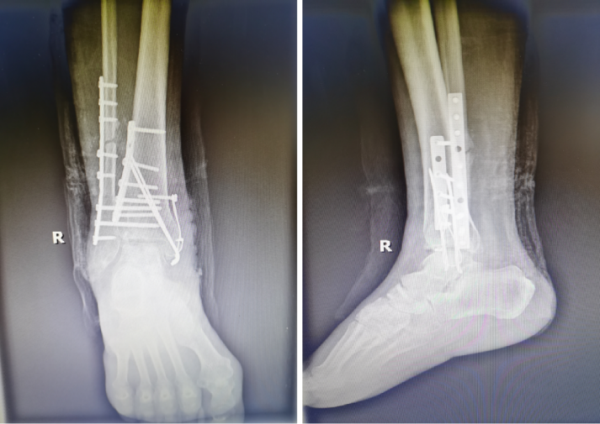

该手术由骨科宋晓飞与龙俊任两位医生共同完成,历时2小时,顺利完成了关节清理、截骨矫形、植骨等一系列手术,恢复了后足力线和踝关节稳定性,术中外观恢复正常,患者和家属对治疗结果非常满意,目前患者正在积极的康复治疗中。